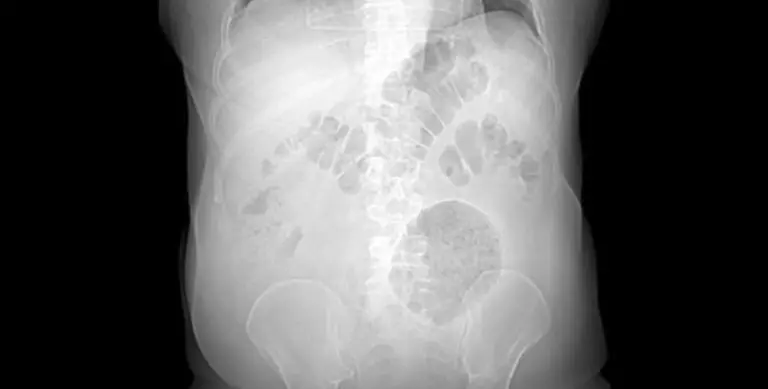

Tomografia computadorizada mostra divertículo gigante

Legenda: O tamanho do divertículo foi constatado por meio de tomografia computadorizada

A formação encontrada tinha 13 cm x 12 cm x 10 cm, quando, em média, esse tipo de inflamação tem entre 4 cm e 9 cm de diâmetro

De acordo com Alexandre, o paciente chegou ao hospital pela porta da emergência, se queixando de dores abdominais e perda de peso há pelo menos dois meses. O exame clínico indicou a presença de uma massa flácida, palpável e dolorosa no flanco esquerdo do abdômen do homem. O tamanho da inflamação foi detectado por uma tomografia computadorizada.